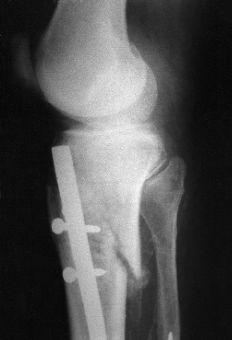

El tiempo medio operatorio fue de 63 minutos (mínimo: 45 y máximo: 90 minutos). Se utilizó un clavo de 8 mm en 29 casos y de 9 mm en 32; se produjo una fractura intraoperatoria de la cortical posterior (Fig. 1). La dinamización se llevó a cabo en una media de 9 semanas (mínimo: 5 y máximo: 20 semanas). La carga completa postoperatoria se inició a una media de 8 semanas (mínimo: 1 y máximo: 19 semanas) tras la intervención. Catorce (6,2%) de los 226 tornillos empleados se doblaron o rompieron (tres tornillos estáticos proximales, uno dinámico proximal y 10 tornillos distales). En tres pacientes el clavo no fue dinamizado antes de cargar peso. En uno de ellos se rompieron todos los tornillos y en dos se rompió el estático proximal y los dos distales (Fig. 2). En tres pacientes se rompieron los tornillos distales a pesar de que el clavo había sido dinamizado.

Figura 1. Rotura intraoperatoria de la cortical posterior de la tibia.Postoperatoriamente no hubo ningún síndrome compartimental, infección, embolia grasa o complicación neurológica. Dos pacientes desarrollaron distrofia simpaticorrefleja, tres presentaron un acortamiento de 6-10 mm y 13 pacientes (21%) desarrollaron dolor femoropatelar que desapareció al retirar el clavo. Todos los pacientes presentaron una movilidad completa de la rodilla. Hubo cuatro casos de rigidez del tobillo con falta del 20% de extensión. Sesenta pacientes (98%) volvieron a caminar sin claudicación y sin bastones y a subir escaleras normalmente. Todos ellos recuperaron su nivel de actividad previa a la fractura.